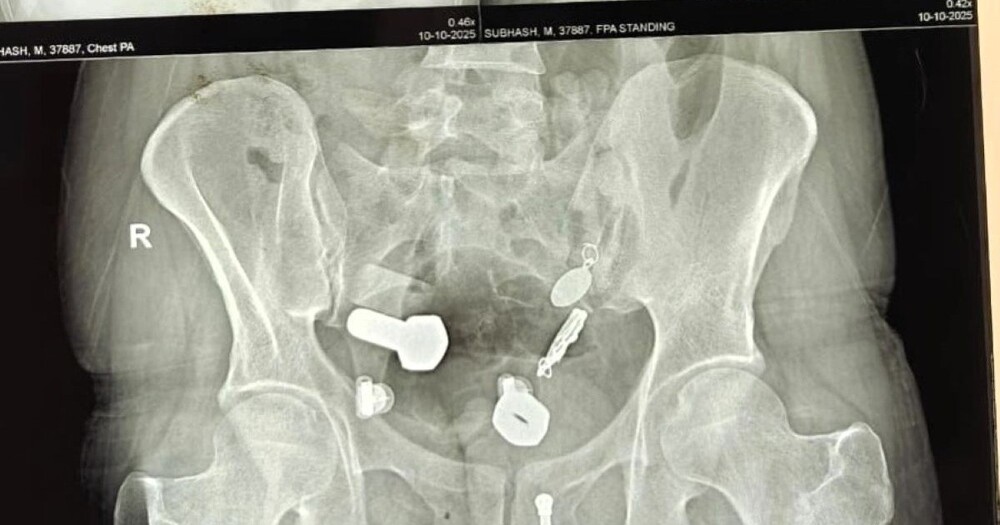

Родственники привезли 34-летнего мужчину в больницу, когда он почувствовал сильную боль в животе и не мог есть и пить. Сканирование показало, что в его пищеводе застряли часы, а в толстом кишечнике оказались металлические фрагменты, гайки и болты.